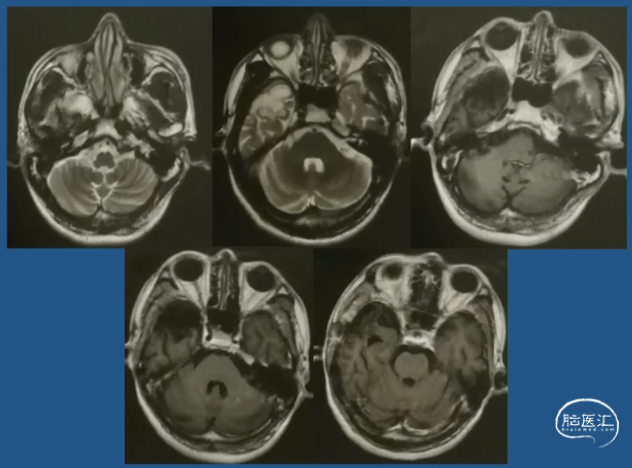

病例示例3 -简要病史

•患者,女性,20岁,右利手

•起病年龄:出生4月

•主要发作形式:伴有知觉受累的局灶性发作

-发作主要表现:发作前偶伴心悸、胸闷→后出现意识丧失伴眼神呆滞→数秒后出现身体向各方向不自主扭转,伴喉部发声(无四肢抽搐表现)→发作持续5-10min后意识恢复→发作后无头痛、头晕等不适

-【出生4月起】:初始发作频率1次/天,服用CBZ后发作可控;

-【12岁起】:发作频率再次↑为1次/天,加用药物后发作控制于5-10次/年;

-【19岁起】:多药联用控制不佳,发作频繁时可达3-4次/天,至少2-3次/月

•20岁时AEDs服用:CBZ 0.2g tid + LTG 100mg bid +CZP 0.5mg qn po

影像学表现:2018-03-05 MRI 常规MRI阴性

术后影像

•神经节细胞胶质瘤Gangliogliomas(GG)

•归类:神经元和神经元-神经胶质肿瘤类,WHO Ⅰ级

•局灶性皮质发育不良(FCD)Ⅲb型